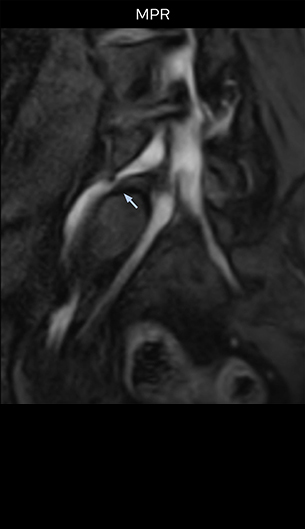

“In such case, we would then browse through axial T2-weighted MR images slice by slice and mentally reconstruct the actual situation based on both radiculography and MRI. Fortunately, NerveVIEW can now very well show nerve courses and presence of nerve compression or edema in one single image series.” “We have often seen NerveVIEW directly depict details of the nerve compression that were not observed by radiculography. Therefore, we think that with NerveVIEW we can reduce the number of invasive examinations, especially for some patients with lumbar plexus symptoms.”

“Before NerveVIEW, diagnosis by MRI alone was sometimes difficult, unless there was a strong suspicion based on clinical symptoms,” says Shoji Yabuki, MD, DMSc, Orthopedic surgeon at Fukushima Medical University School of Medicine. “This is why we routinely perform selective lumbosacral radiculography (nerve root block) and x-ray in such cases. However, radiculography can only depict nerves as far as the contrast agent reaches. When a nerve is distorted by compression, the contrast agent will not pass through this compressed area, preventing us from evaluating the full nerve compression.”

The key concept in MR neurography, Dr. Yabuki stresses, is the ability to directly visualize spinal nerves, versus inferring the presence of pathology indirectly. “Before NerveVIEW, we estimated compression of the nerve by looking for the presence or absence of fat signal on other MR images,” he says.

“For example, in sagittal images, when the presence of fat is observed in the intervertebral foramen, it suggests that there is a margin around the nerve. Similarly, the absence of fat indicates that the nerve is being compressed. So, we used to deduce nerve compression indirectly. With NerveVIEW, however, we can observe the condition of the nerves directly, regardless of the presence or absence of fat. We always prefer such direct observation of anatomy over having to make an inference about it.”

“Although symptoms of typical disc herniation and atypical hernia are very similar, the actual site of herniation is different. It is therefore important to characterize the nerve’s condition both inside and outside of the intervertebral foramina. “Conversely, if we see no abnormality in NerveVIEW, we can assume at least that there is no severe condition that requires surgery. Like this, it can help us avoid unnecessary surgery. NerveVIEW can have a tremendous impact in this way.”

“NerveVIEW is really useful for those cases where a nerve disorder is strongly suspected based on the clinical examination but our regular MRI images do not show any findings. These atypical herniations and spinal canal stenosis, occurring in 5% to 15% of the total lumbar herniation/stenosis cases are our main target when using NerveVIEW,” says Dr. Yabuki.